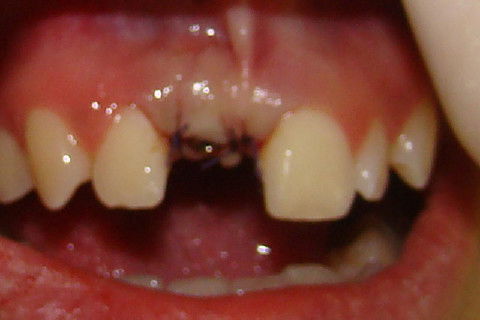

Foto frontal da paciente antes da reabertura